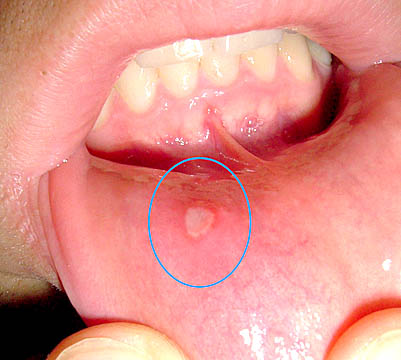

Dạng phổ biến là nhiễm virus Herpes ở môi, hay còn gọi là đau do lạnh hoặc sốt mụn nước (vì lâm sàng bệnh nhân hay có dấu nhiễm trùng đi kèm), điển hình xảy ra ở môi, màu đỏ sậm và không thuộc phổ của loét miệng. Dạng ít gặp là dạng nhiễm Herpes miệng, nhiều khi nhiễm Herpes miệng nhưng không triệu chứng và không nhận thức được có nhiễm bệnh. Về lâm sàng, chẩn đoán phân biệt chính của RAS là nhiễm virus Herpes simplex. Đặc điểm chính để phân biệt là vị trí tổn thương:

-RAS thường xảy ra trên vùng niêm mạc lỏng lẻo, không bị sừng hóa như: niêm mạc má, môi, sàn miệng,và mặt dưới lưỡi;

-Loét do Herpes xảy ra ở niêm mạc bị sừng hóa, có liên quan mật thiết với quá trình nhai: khẩu cái cứng, lợi, mặt lưng lưỡi, tùy theo vùng chấn thương;

-Nhìn chung, RAS phổ biến hơn nhiễm Herpes miệng tái phát, tổn thương của RAS không có giai đoạn mụn nước và thừơng kích thước lớn hơn loét do Herpes;